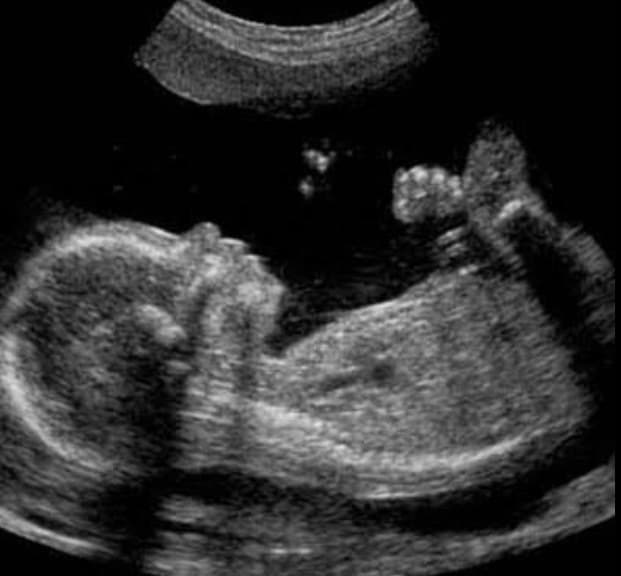

मुजफ्फरनगर . जन्म से प्रसव जांच की शिकायत पर हरियाणा पुलिस ने मुज़फ्फरनगर के एक चर्चित अल्ट्रासाउंड सेंटर पर छापेमारी की। इस दौरान हरियाणा पुलिस के साथ साथ मुज़फ्फरनगर के पुलिस और प्रशासनिक अधिकारी भी मौके पर मौजूद रहे। शिकायत सही पाए जाने पर अल्ट्रासाउंड सेंटर की मशीनें सीज कर दी गई हैं। हरियाणा पुलिस मौके से कंप्यूटर का डाटा भी पुलिस अपने साथ ले गई. मामले में थाना सिविल लाइन में मुकदमा दर्ज कराते हुए जांच शुरू कर दी है।

सिविल लाइन थाना क्षेत्र में देर रात हरियाणा पुलिस की टीम मुज़फ्फरनगर पहुंची। यहां हरियाणा पुलिस ने मुजफ्फरनगर पुलिस काे अपने साथ लिया। पुलिस और प्रशानिक अधिकारियों को साथ लेकर सर्कुलर रोड स्थित एक प्राइवेट अल्ट्रासाउंट में छापेमारी की। हरियाणा पुलिस को इस अल्ट्रासाउंड सेंटर पर नियम विरुद्ध जन्म पूर्व गर्भ की जांच किए जाने की शिकायतें मिल रही थी। इसी को लेकर हरियाणा पुलिस ने देर रात छापेमारी करते हुए कार्यवाही की। बताया जा रहा है कि अल्ट्रासाउंड केंद्र से कई ऐसे सबूत मिले हैं जो इस बात की गवाही दे रहे हैं कि यहां पर गर्भ की जांच हो रही थी।